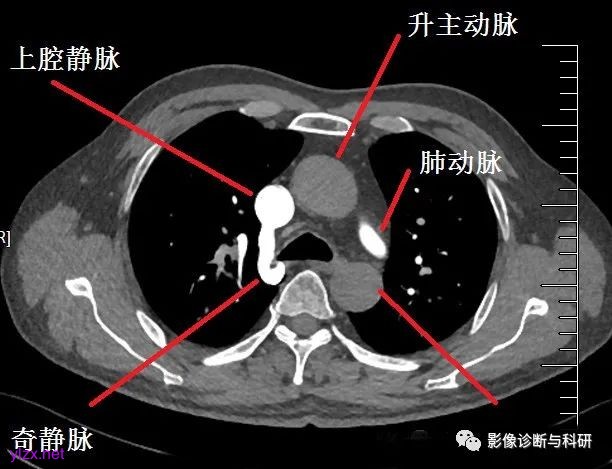

在第12胸椎体前,奇静脉由右腰升静脉、右肋下静脉形成,肋下静脉在右膈肌脚后的第12胸椎右前方,奇静脉在后纵隔上升到第4胸椎的水平,在右肺门后面弯向前上方汇入上腔静脉。

奇静脉的上端注入上腔静脉,而下端起自下腔静脉系的腰升静脉。因此,奇静脉是沟通上、下腔静脉的重要通道之一。当上腔静脉或下腔静脉回流受阻时,则上述通道即成为重要的侧副循环途径之一。